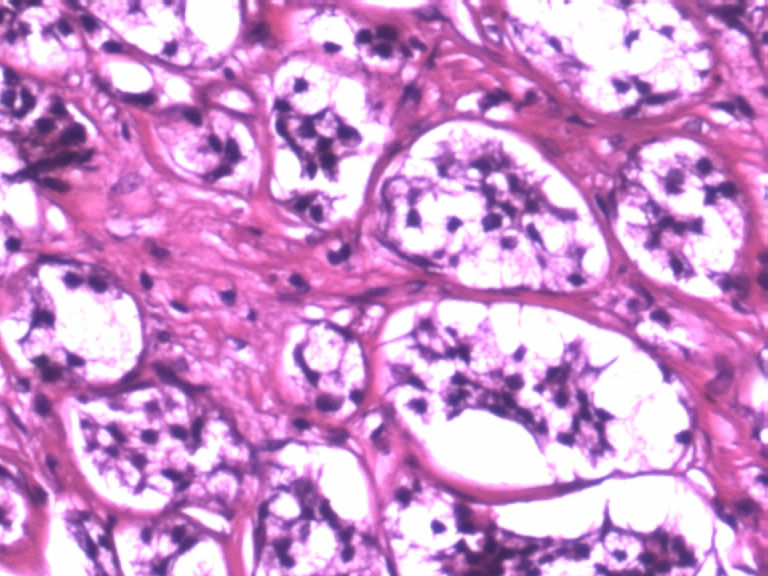

男,50岁,阑尾长7厘米,直径0.4---0.6厘米。剖开:尖端看见淡黄色区,不规则,界限欠清,0.15*0.2厘米,质中。

• 您看了吗?阑尾类癌?图1

图1

×参考诊断

考虑阑尾类癌

像类癌,有些粘液,标记一下Syn、CgA,有可能是杯状细胞类癌

看不太清楚,有些结构有点像类癌。

类癌,

按照胃肠胰腺神经内分泌肿瘤WHO2010分类,该例应属于NET G1(神经内分泌瘤,1级)。需标记Syn, CgA, Ki67.

倾向神经内分泌肿瘤,建议做CgA、SYN、Ki-67检查。

阑尾的神经内分泌肿瘤我们已经碰到好几例了,一般都在阑尾尖端,取材一定要规范,这样可以减少漏诊率。